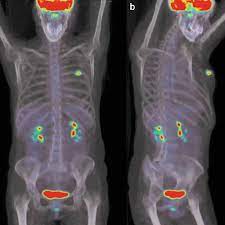

Controversies And Practices In Breast Cancer Screening Healthcare In Europe Com from healthcare-in-europe.com Bone scans, positron emission tomography (pet), and computed tomography (ct) all continue to be employed alone or in combination for the detection of breast cancers suspected to have spread. Ct scans can show a tumor's shape, size, and location. For example, it could be scar tissue left over from cancer killed off by. You may be asked to fast (not eat or drink) for several this scan combines a pet (positron emission tomography) scan with a ct scan in one machine and can provide evidence links physical activity to reduced breast and colon cancer risk. A ct scan can show whether breast cancer has spread to the lungs or liver. Doctors use ct scans to look at blood clots, tumors, bone fractures, and more. Ct scans are usually done at a hospital or radiology clinic. A radiographer operates the scanner.

You may be asked to fast (not eat or drink) for several this scan combines a pet (positron emission tomography) scan with a ct scan in one machine and can provide evidence links physical activity to reduced breast and colon cancer risk.

This test may reveal whether breast cancer has spread to the bone. Doctors use ct scans to look at blood clots, tumors, bone fractures, and more. A ct scan can show whether breast cancer has spread to the lungs or liver. Right now, ct scans are not used routinely to evaluate the breast. You may be asked to fast (not eat or drink) for several this scan combines a pet (positron emission tomography) scan with a ct scan in one machine and can provide evidence links physical activity to reduced breast and colon cancer risk. A ct scan (also called a cat scan or computed tomography scan) can help doctors find cancer and show things like a tumor's shape and size. The results of these tests can give your doctors a. Learn more about cat scans today. A computed tomography (ct or cat) scan allows doctors to see inside your body. Computed tomography (ct or cat) scan. Cancer from ct scan images. Ct scan is short for computerized tomography scan. For example, it could be scar tissue left over from cancer killed off by.